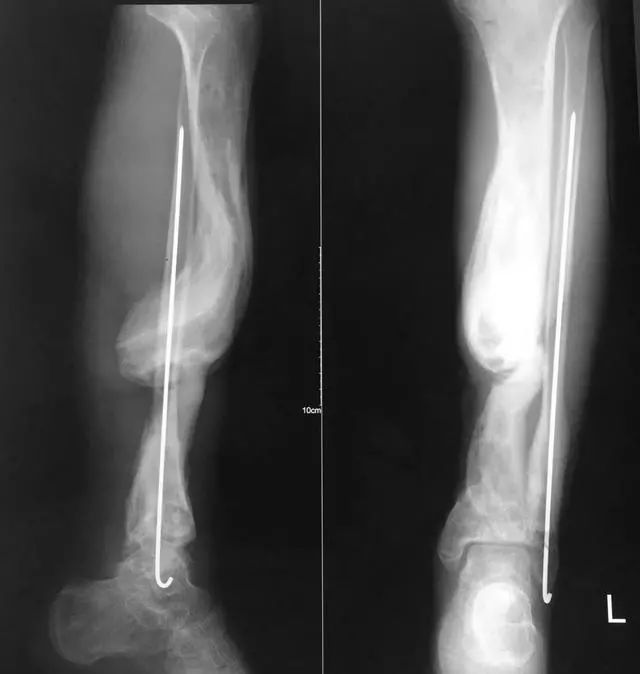

下面1例是我的学生所发。病史清楚,跗骨骨折后伤口开放,每次换药用双氧水冲洗伤口,造成骨坏死

跗骨感染

该例患者需要汲取的经验和教训:不要使用双氧水冲洗伤口死骨密度高是因为不参与代谢周围骨疏松治疗清理死骨后用骨水泥诱发诱导模反复几次做半开放植骨手术后走路刺激骨愈合,改善骨质愈合。